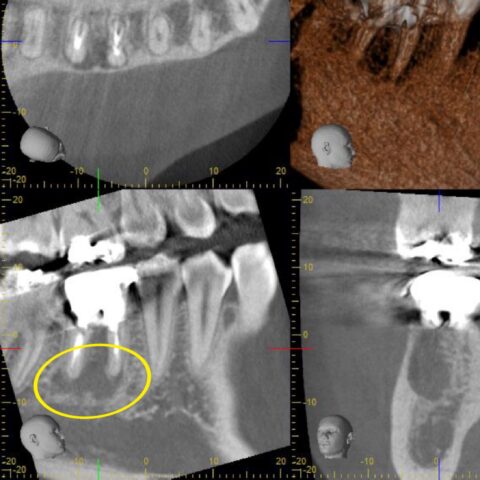

↓CT

根の先が黒くうつっており

かなり大きな「根尖病変」があります。膿が溜まって、歯を支えている骨が溶けている状態です💦

根管に神経の取り残しがあり感染根管治療をご提案しました。